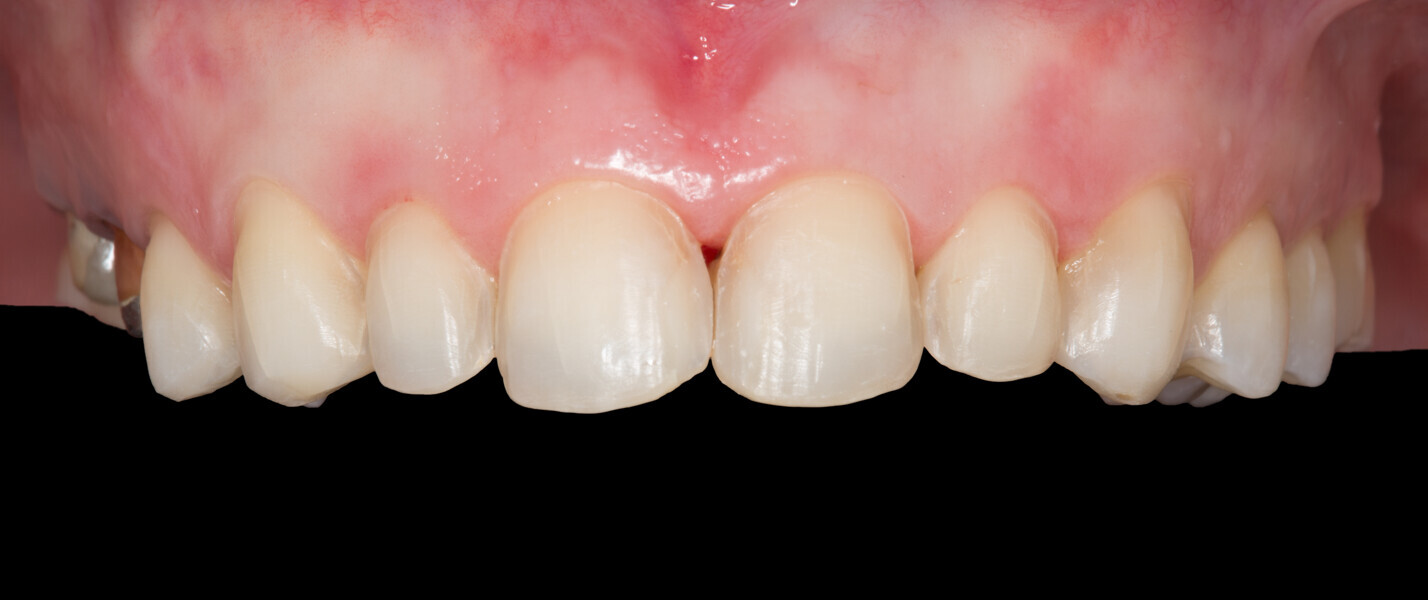

Fig. 3: Initial clinical situation.